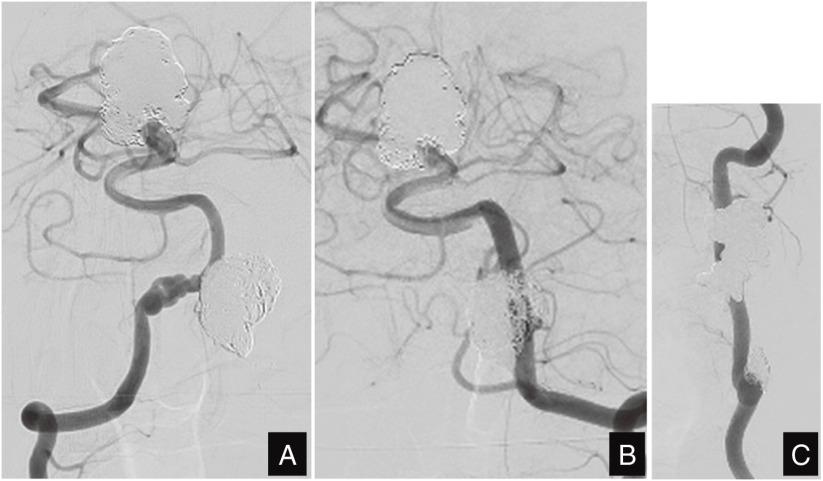

A 41-year-old man presented with left hemiparesis. He had a giant thrombosed aneurysm at the basilar artery-superior cerebellar artery (BA-SCA) junction and a left extracranial VA aneurysm. A VA fusiform aneurysm developed during a 1-month interval following the first session of intravascular coil embolization for the BA-SCA aneurysm. Stress on the fragile artery due to FMD during micro-catheterization may have caused the aneurysm. An anomalous aortic origin of the left VA may also have played a role in the formation of the large aneurysm and extracranial VA aneurysm. We performed overlapping stent-assisted coil embolization for the VA fusiform aneurysm using an Enterprise VRDs, and coil embolization for the BA-SCA thrombosed aneurysm using the stent-assisted technique with an Enterprise stent. Both aneurysms remained occluded for 7 years.

一名41岁男性出现左侧偏瘫。他在基底动脉-小脑上动脉(BA-SCA)交界处有一个巨大的血栓形成的动脉瘤以及一个左侧颅外VA动脉瘤。在对BA-SCA动脉瘤进行首次血管内线圈栓塞后的1个月内,一个VA梭形动脉瘤形成。微导管插入过程中FMD对脆弱动脉造成的压力可能导致了动脉瘤的形成。左侧VA的主动脉异常起源也可能在大型动脉瘤和颅外VA动脉瘤的形成中起了作用。我们使用Enterprise VRDs对VA梭形动脉瘤进行了重叠支架辅助线圈栓塞,并使用Enterprise支架的支架辅助技术对BA-SCA血栓形成的动脉瘤进行了线圈栓塞。两个动脉瘤均闭塞7年。